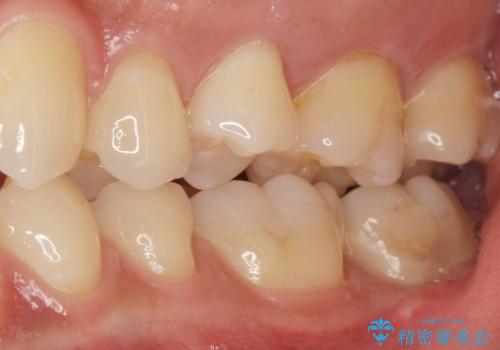

- 奥歯にフロスを通すとにおいがすることを気にされ、来院された患者様です。

精査したところ、奥歯に充填された保険内のコンポジットレジンの適合が悪いことにより、汚れがたまりやすい状態でした。

不適合なレジンを除去し、セラミックインレーによる治療を行いました。(右上76左上67右下7の計5本)